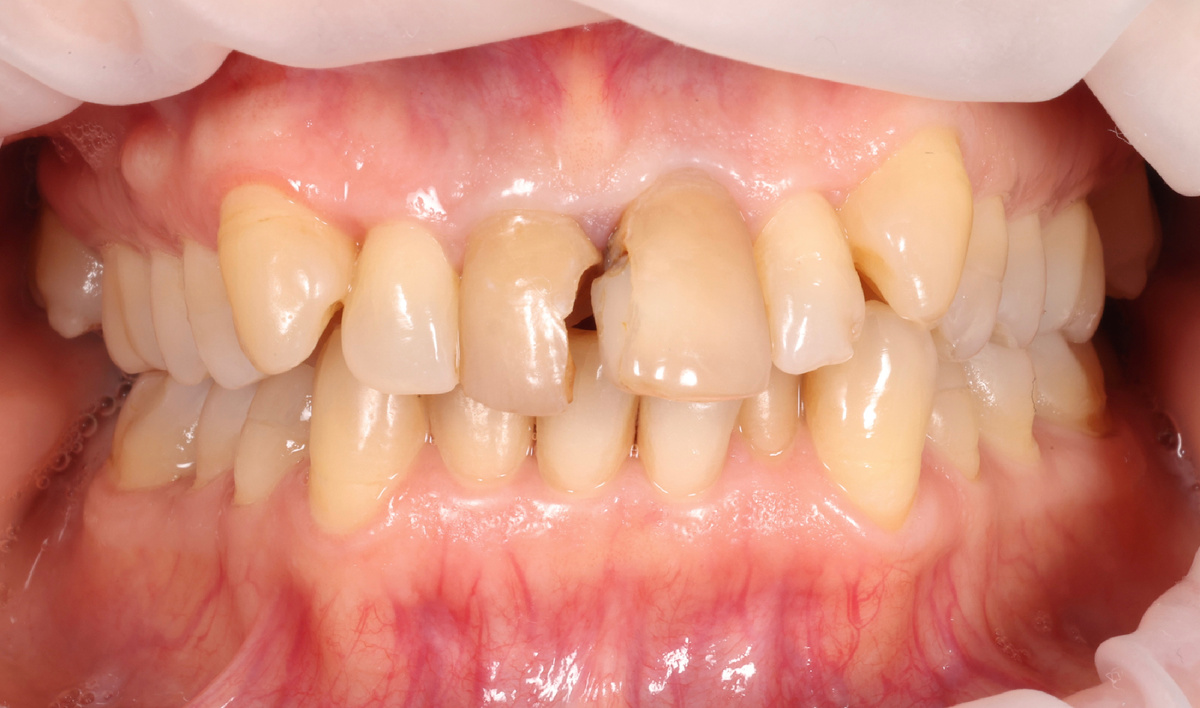

Пациентка обратилась с разрушенными фронтальными зубами - центральные резцы верхней челюсти требовали капремонта:

Разрушенные коронковые части зубов 1.1 и 2.1

Коронковые части пострадали серьёзно, зубы требовали восстановления коронками. Почему так жёстко? Да потому что от родных тканей мало что осталось. Старые пломбы за "родные ткани", если что, не считаются.

Прикус у пациентки далёк от идеала, это факт. Один из зубов (2.1) был выдвинут и наклонён вперёд относительно соседнего 1.1. Перекос заметен.